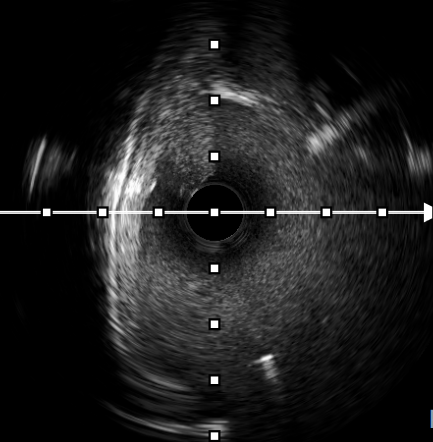

手术在神经内一科副主任胡军和刘军主任医师指导下进行,贾瑞华副主任医师主刀,介入导管室、麻醉科等多学科团队紧密协作。术中,通过股静脉穿刺,将导管送入狭窄的静脉窦内,在血管内超声(IVUS)指导下精准测量狭窄段的长度和直径后,将支架顺利释放并展开,成功覆盖狭窄部位。术后即刻造影显示,狭窄的静脉窦完全开通,血流恢复正常,患者术后恢复良好,头痛和视力模糊的症状消失,术后第3天顺利出院。